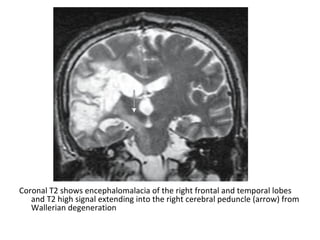

-Infarct involvement of the corticospinal tract may

cause mass effect , mild hyperintensity on T2 and

eventual atrophy of the ipsilateral cerebral peduncle

& ventral pons due to Wallerian degeneration , these

changes can first be seen in the subacute phase with

atrophy being predominant feature in the chronic

stage (See later)

Coronal T2 shows encephalomalacia of the right frontal and temporal lobes

and T2 high signal extending into the right cerebral peduncle (arrow) from

Wallerian degeneration